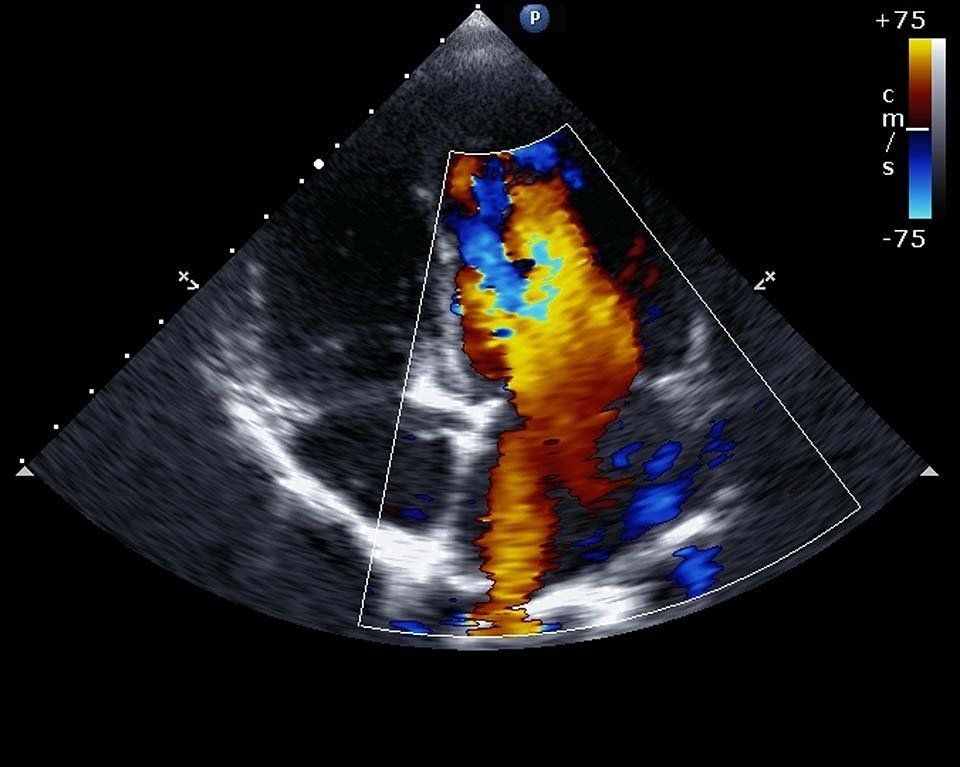

L'ecografia color-doppler ha questo nome perché prevede la colorazione dei vasi sanguigni, consentendo di eseguire un'analisi ancora più dettagliata e immediata del flusso ematico. Presso la struttura si eseguono:

Le ecografie color-doppler sono eseguite dal personale qualificato dello Studio Radiologico Dr. Tirelli di Altamura, in provincia di Bari, con macchinari di ultima generazione. Attraverso il duplex-scanner si monitorano l'anatomia e il flusso ematico di vasi sanguigni arteriosi e venosi in tempo reale e in modo contemporaneo.

Con l'ecografo in modalità B-MODE il medico studia la morfologia delle pareti dei vasi e la motilità, individuando eventuali alterazioni. Utilizzando il doppler pulsato, infine, è possibile valutare a livello dinamico il flusso sanguigno in un punto preciso.